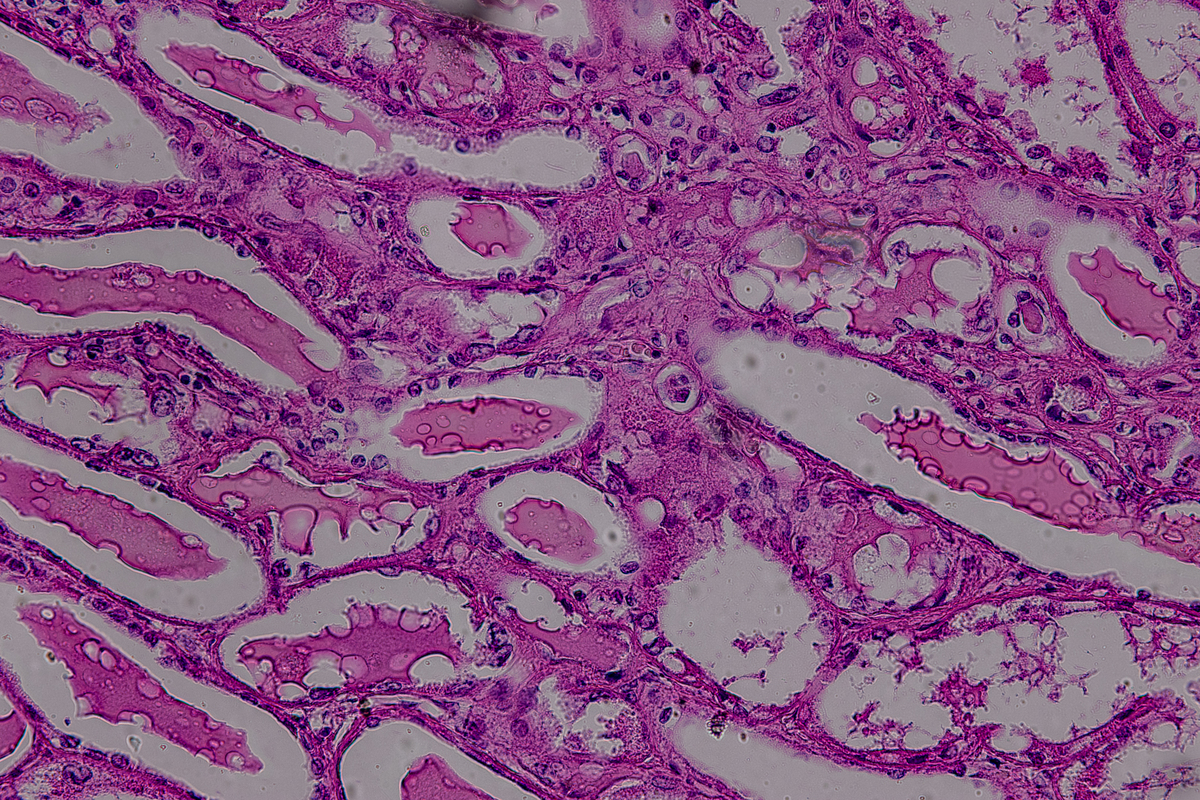

IBD (炎症性肠病) 是一组慢性疾病,包括溃疡性结肠炎 (UC) 和克罗恩病 (CD)。UC 和 CD 都是肠道炎症疾病,但它们有一些不同之处。

UC 是一种炎症性肠病,仅影响结肠,引起病变区域的黏膜层变薄和出血。CD 则可能影响任何肠道部位,包括口腔到肛门的全消化道,常伴随狭窄和溃疡形成。

虽然 UC 和 CD 的病因和症状不同,但它们有一些共同点,如肠道炎症、腹痛、腹泻、便秘等。此外,有些患者可能同时患有 UC 和 CD,这被称为不完全性肠炎。